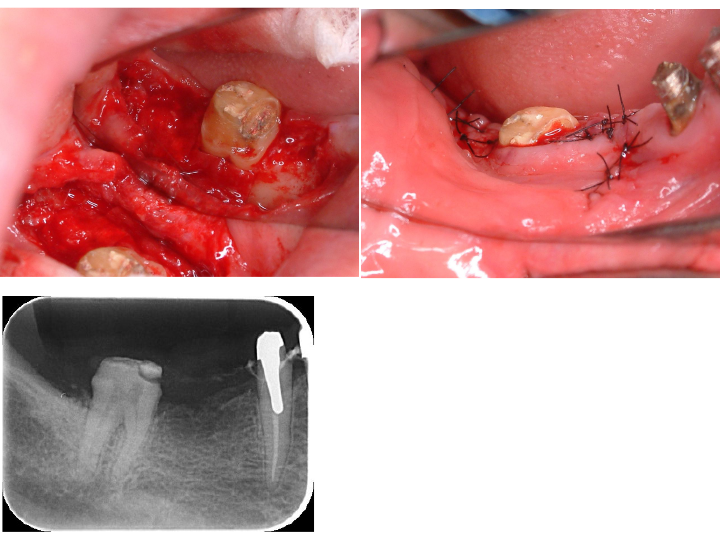

所見:左下7番より排膿を認め、歯周病により歯槽骨の吸収が認められます。また、歯周組織検査により8mmの歯周ポケットが認められます。

デンタルおよびCT所見

歯周病により失われた歯槽骨が骨様組織により改善されているように思われます。

術直後のレントゲン写真です。

術前で破壊されていた部分に骨の再生が認められるため、黒かった部分が白くなっていることがわかります。